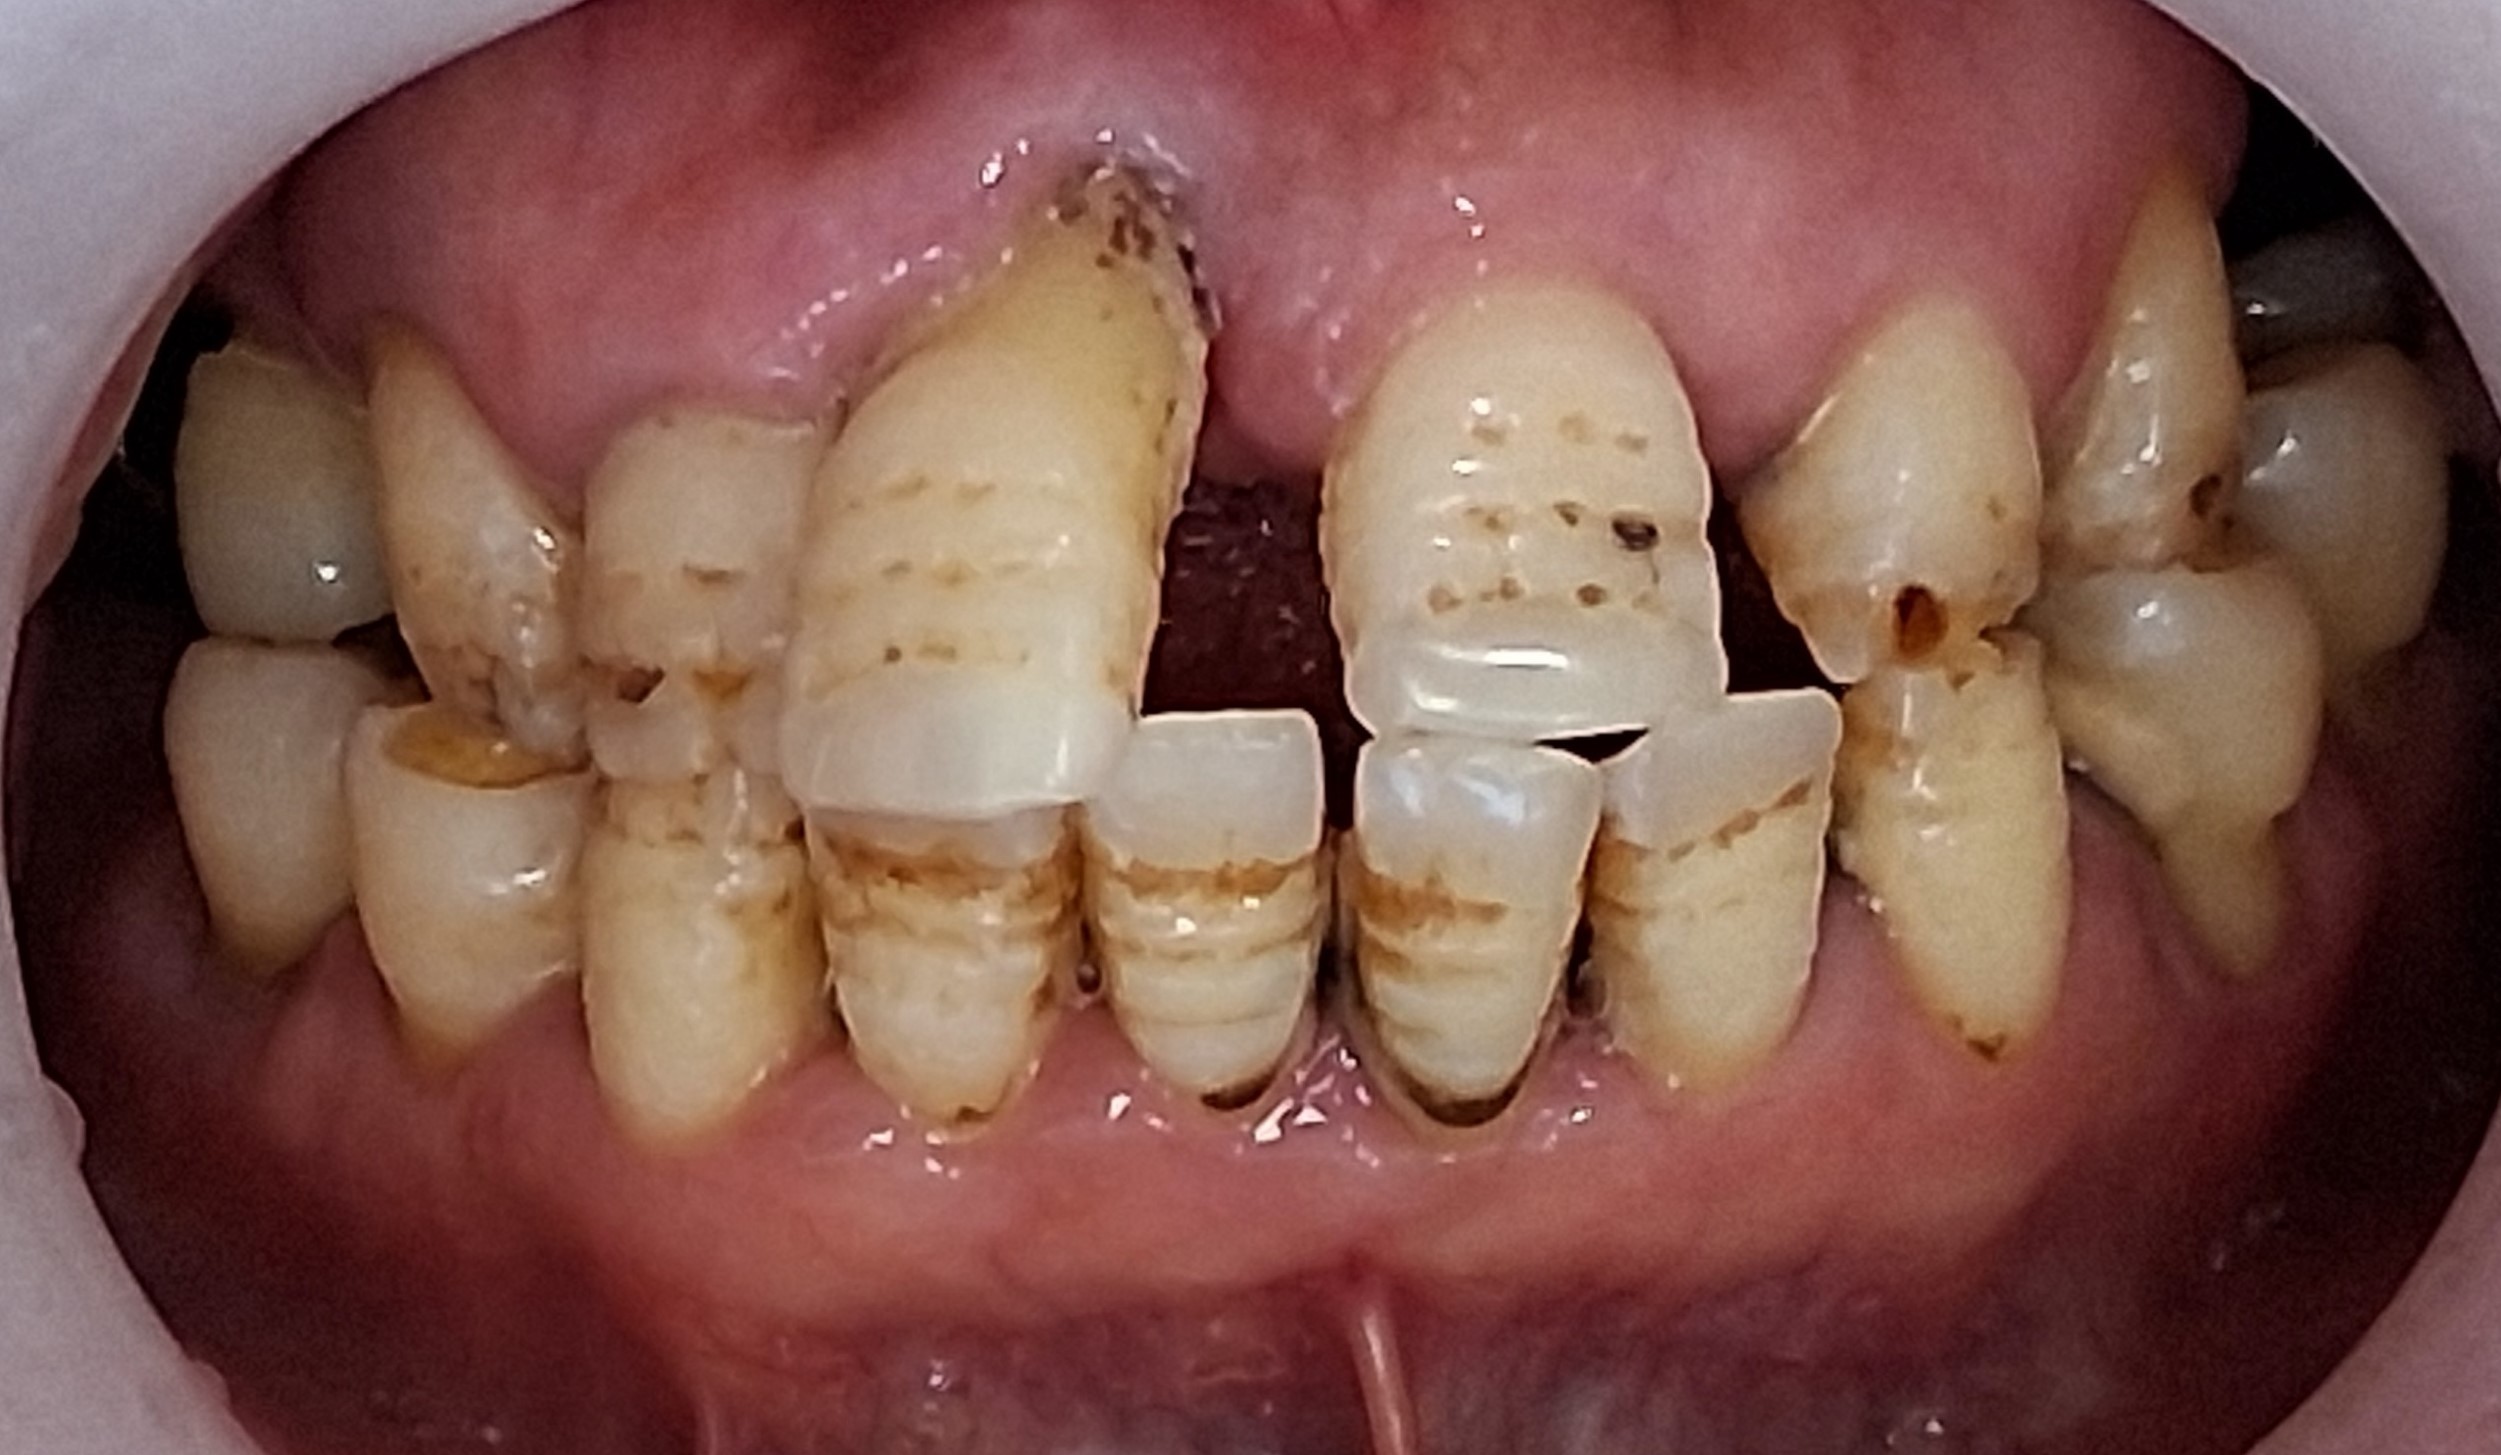

신뢰가 함께한 진료의 순간

환자 한 분 한 분과 함께 쌓아온 소중한 기록입니다

임플란트의 모든 정보가

그대로 전달될 수 있을 때까지